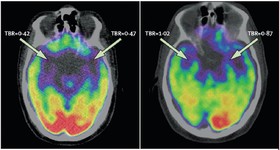

مطالعات محققان نشان میدهد که چطور فعالیتهای هسته آمیگدال یا بادامه مغز با استرس و حمله قلبی مرتبط است.